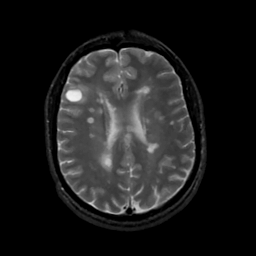

MR Study #8, March 31, 1991 -- Slice #32